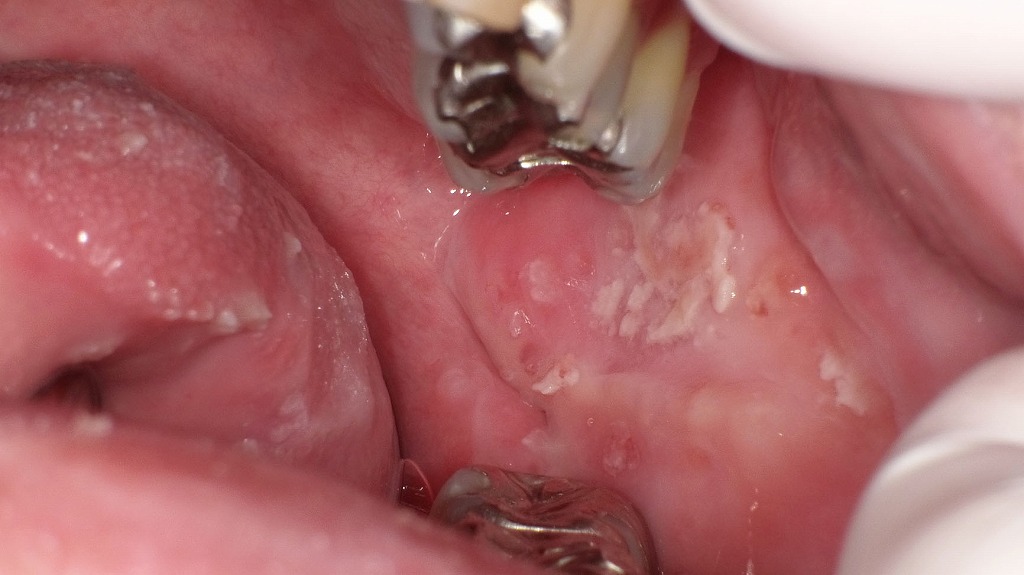

カンジダ性舌痛症の場合、紅斑性(萎縮性)カンジダ症が原因となることがありますが、舌の痛みに見合うような明らかな器質的所見が認められないことが多くあります。

舌や頬粘膜に白色の付着物(白苔)がみられる口腔カンジダ症の症例です。カンジダ菌の増殖により粘膜に炎症が生じ、見た目の変化だけでなく、ヒリヒリ・ピリピリとした舌の痛み(カンジダ性舌痛症)を伴うことがあります。

義歯の使用、免疫力の低下、口腔乾燥などが発症の一因となるため、原因に応じた抗真菌治療と口腔環境の改善が重要です。